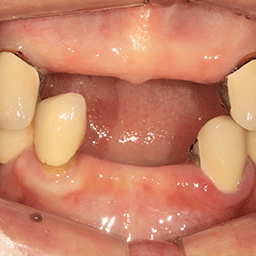

W Dental Clinic Before & After

치료 전후사진

Before

After

뼈이식